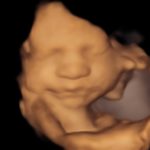

4D/5D/HD Ultrasound Gallery

Gallery